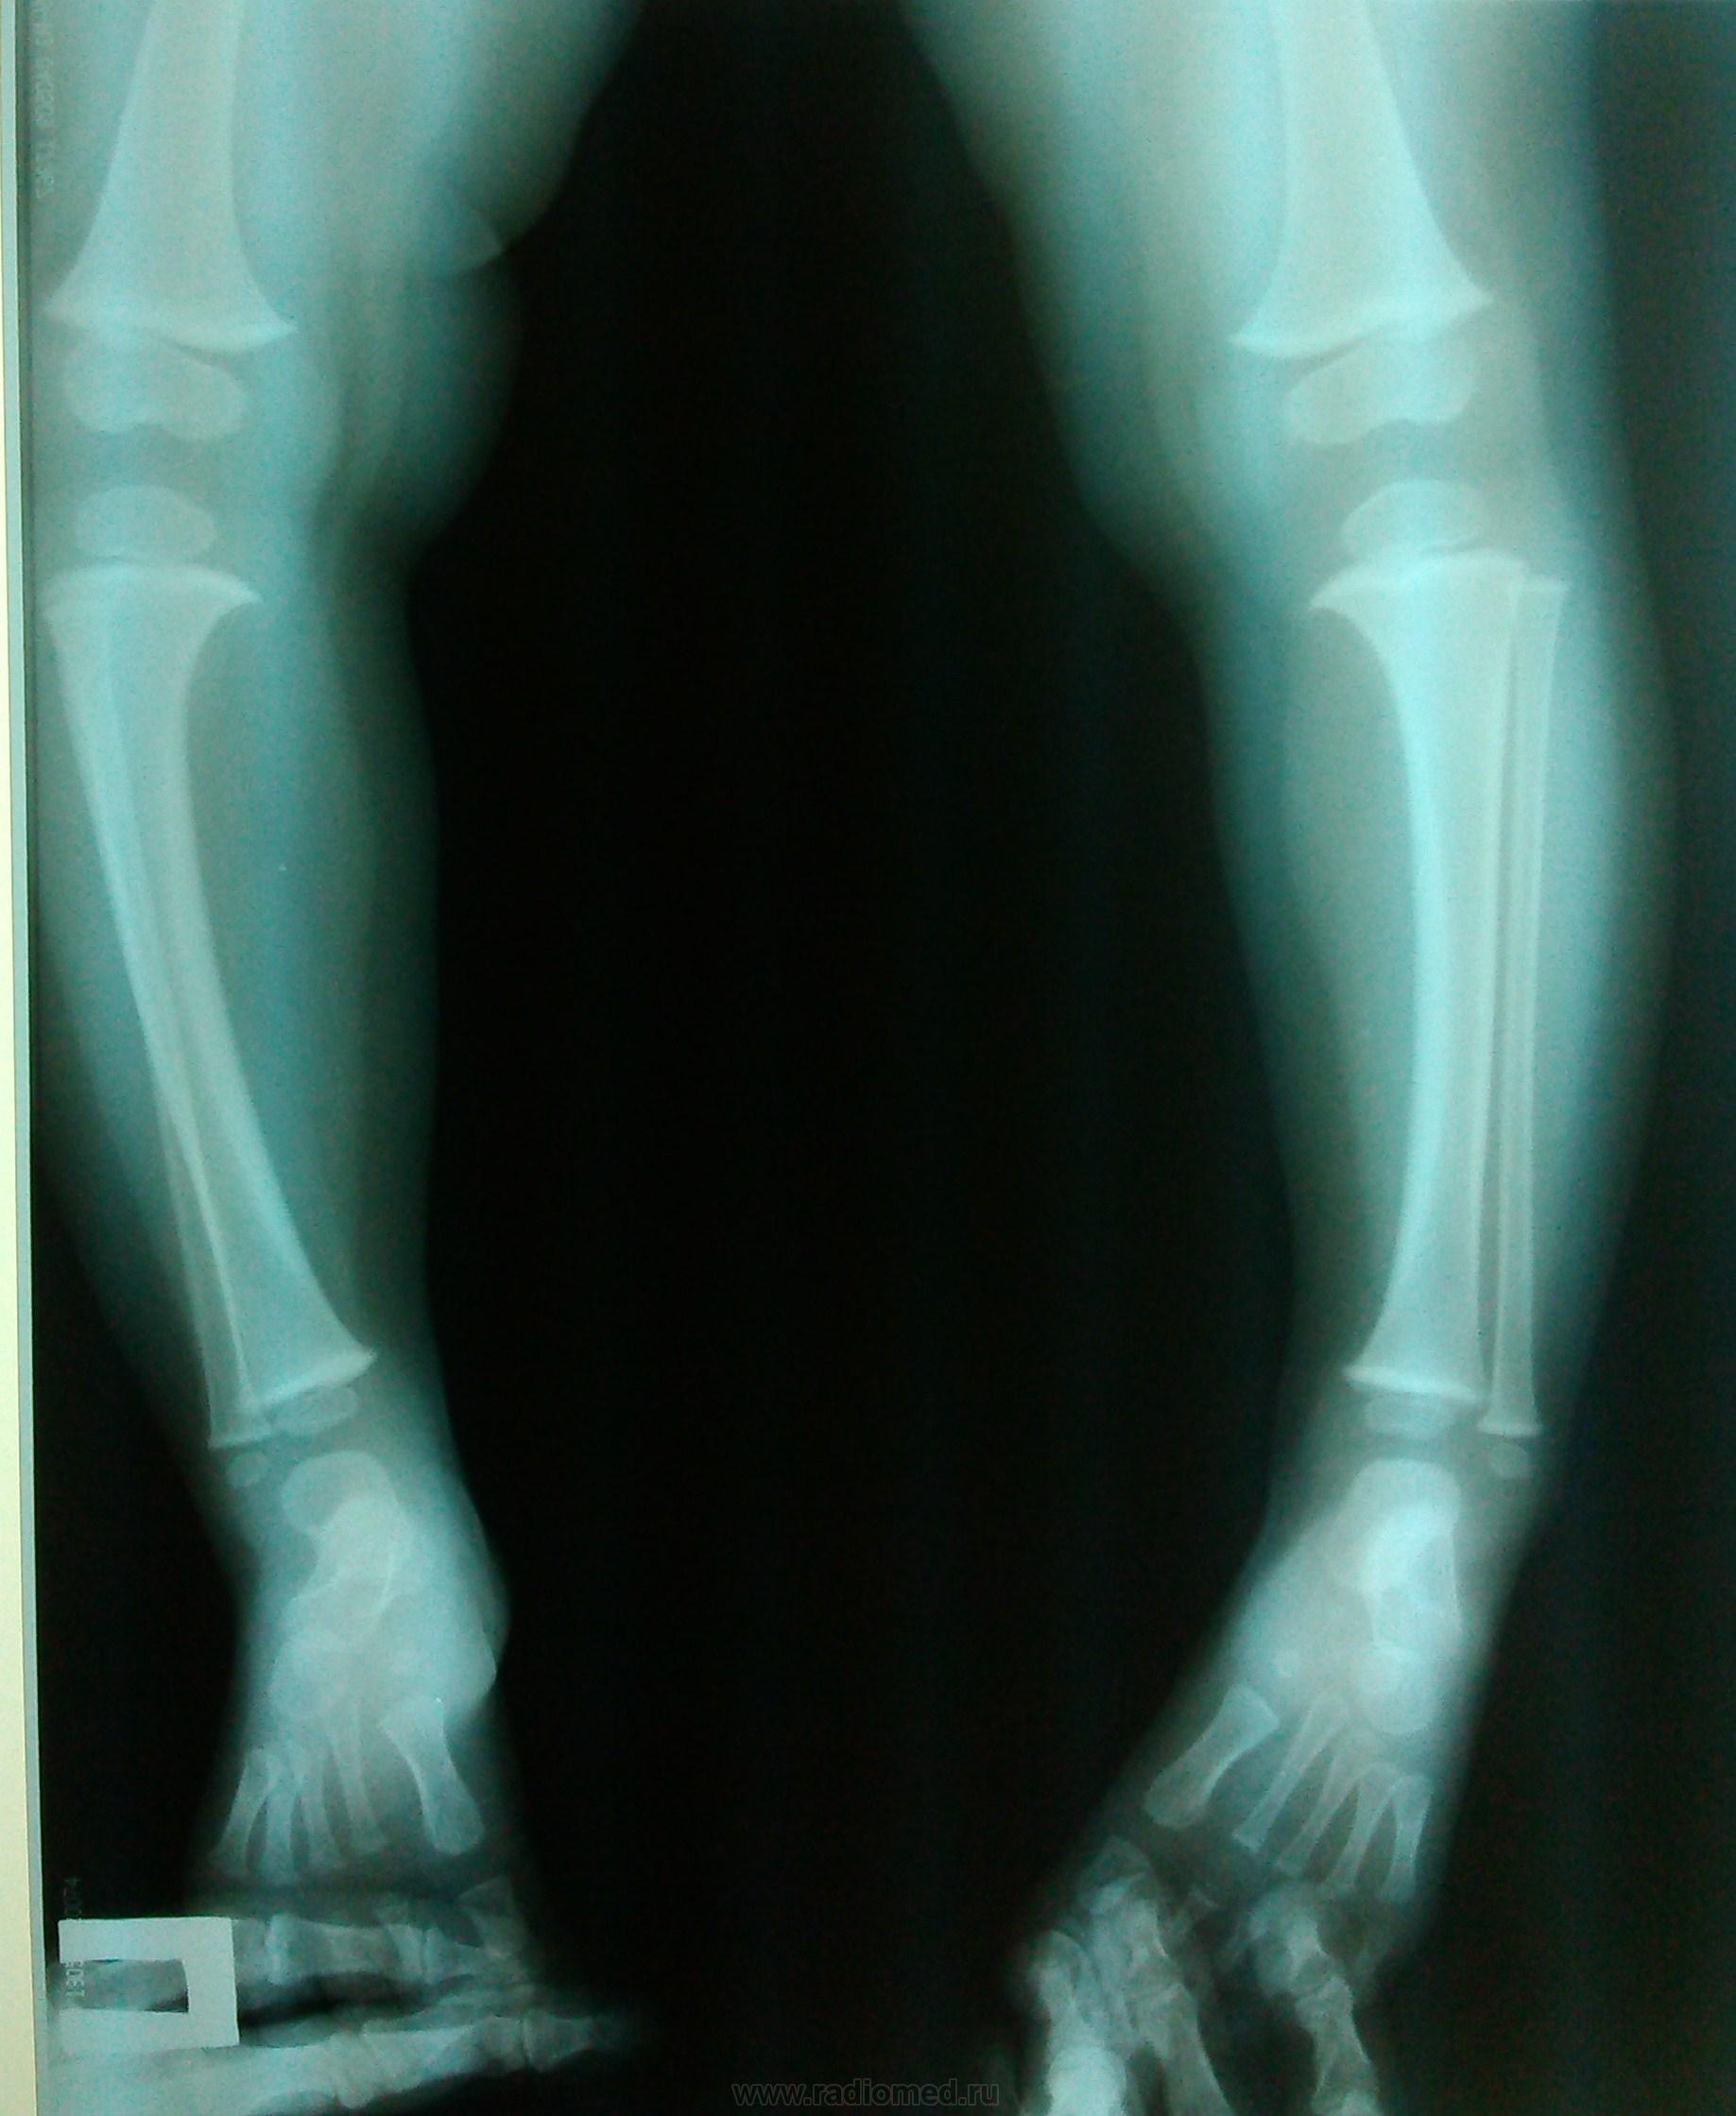

Для диагностики варусной деформации голени врач проводит тщательный осмотр и собирает анамнез, выясняя, когда появились первые признаки и есть ли наследственная предрасположенность. Обязательно выполняется рентгенография голеней, которая позволяет увидеть искривление кости и возможные патологические изменения в колене или стопе, возникающие из-за компенсаторных механизмов. При необходимости врач может назначить дополнительное рентгенографическое исследование тазобедренных суставов и стоп.